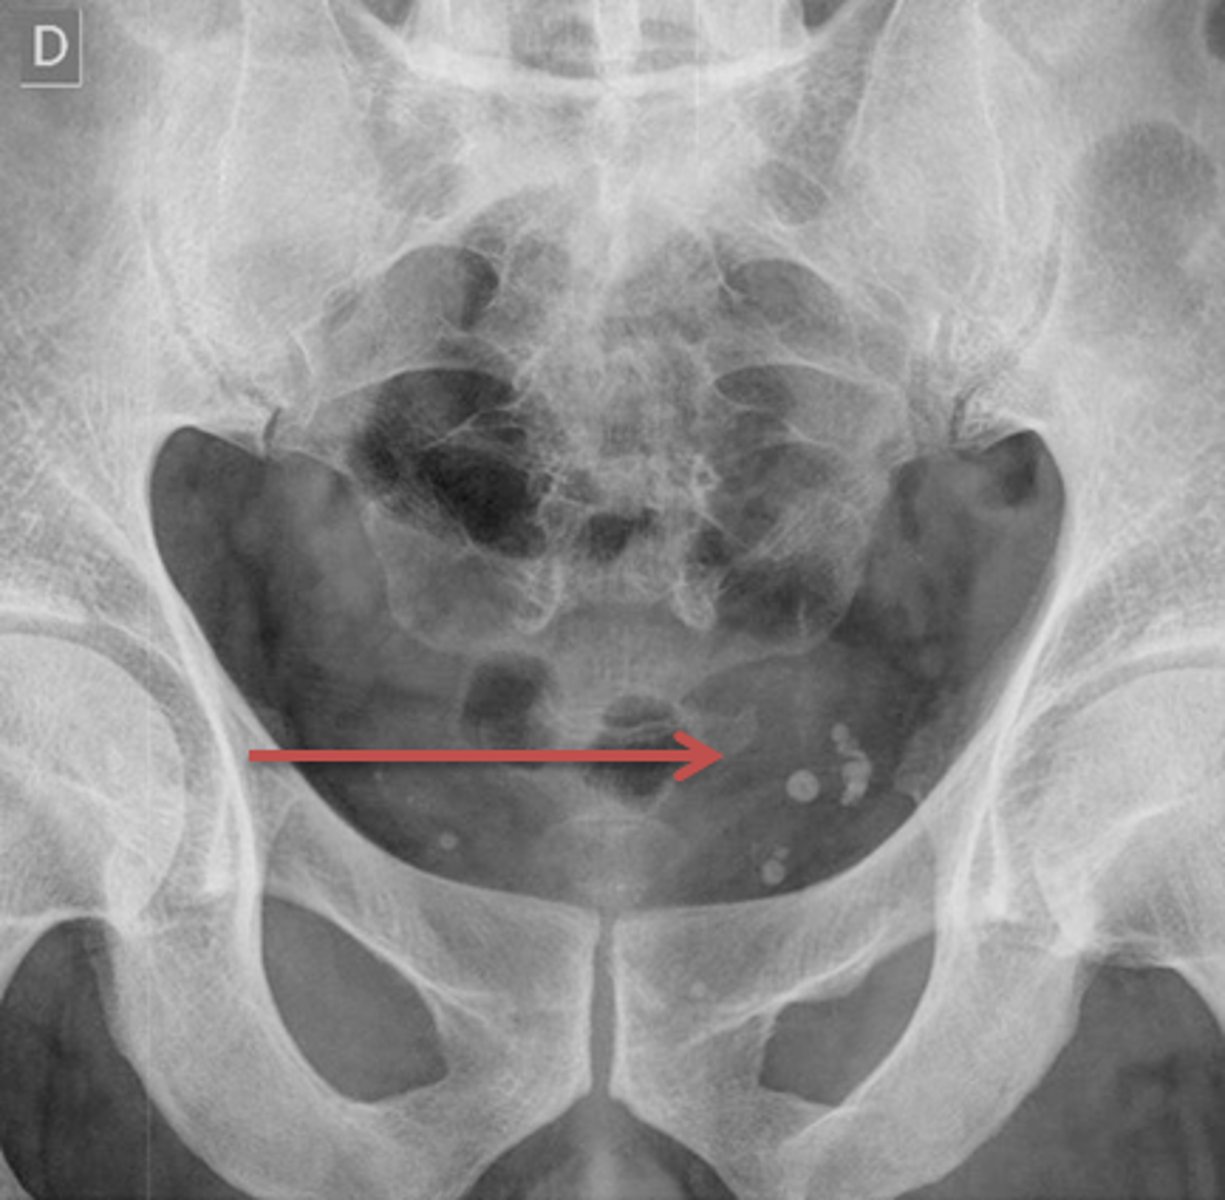

Bladder stones

Kidney stones

Gall stones

Fibroids

Phleboliths